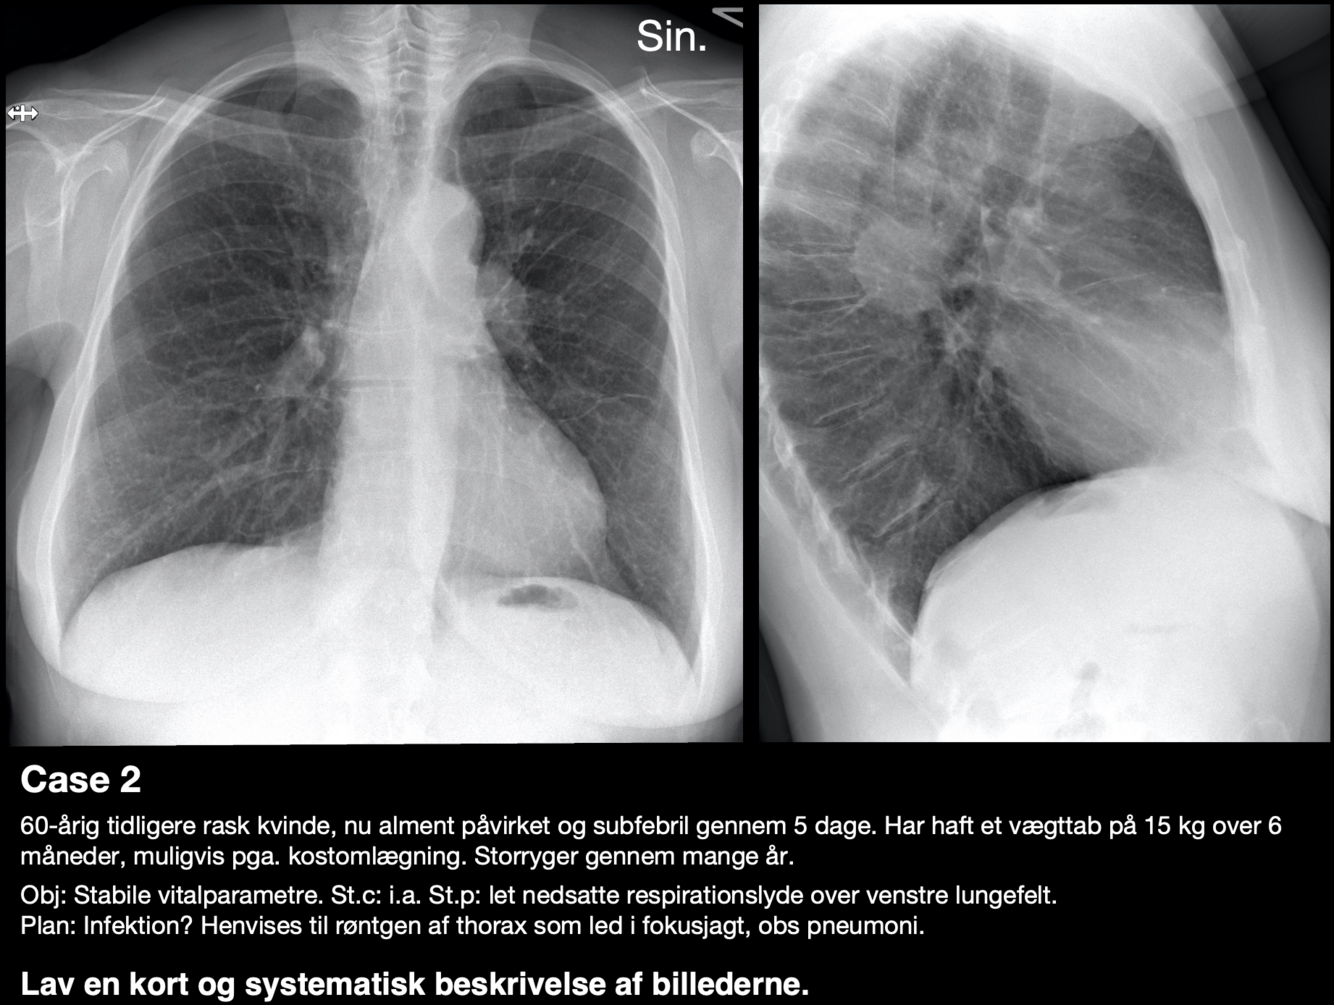

Diagnose?

A

Venstresidig basal pneumoni